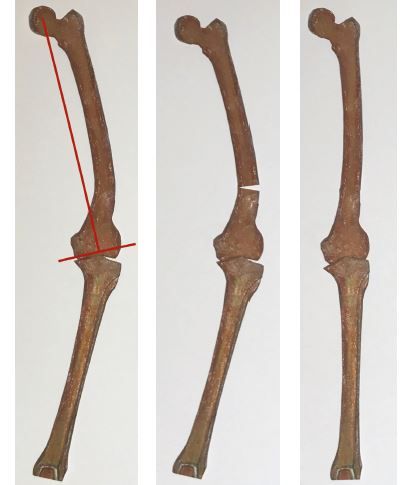

3. Extra-articular femoral and/or tibial deformity needs to be identified and appropriate extra-articular or intra-articular correction performed8

If extra-articular deformity (EAD) is >20 degrees, close to the joint, and resection likely to damage LCL attachment or if the distal tibial axis falls outside of tibial plateau, then EA osteotomy may be required.(Figs 4-6)

- If these are released and deformity persists, it implies that there is a tibial EAD. This should have been detected and anticipated in the planning stage. Obtain a rectangular extension gap by re-cutting proximal tibia. Any residual varus deformity is corrected by closed-wedge osteotomy at apex of deformity usually in the tibial metaphysis.